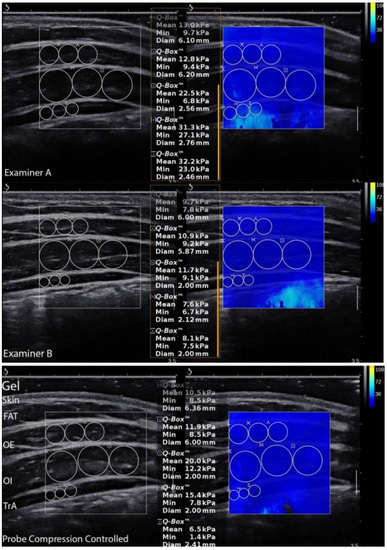

LAMs elasticity was calculated in the ultrasound scanner using the Q-Box quantitative tool after collecting all data (Figure 2). This was used to quantify each muscle shear modulus. Three separate circles were positioned inside the fascial edge of each muscle, and the muscle elasticity within the circle was automatically calculated and depicted in kilopascal (kPa). The mean value of the three separate circles was considered the muscle elasticity value from a given image [16]. In turn, images for LAMs thickness and superficial fat layer measurements were edited and calculated using RadiAnt Dicom Viewer 5.5.1 (Medixant, Poznań, Poland). The edits included enlarging, brightening, and adding contrast. The vertical marking line positioned 20 mm from the musculofascial junction of the TrA was consistently used to re-measure the thickness for each muscle (Figure 3). The vertical distance between the musculofascial layers represented the individual thickness of the oblique external (OE), oblique internal (OI), and TrA [24,30].

Figure 2.

Ultrasound scans of the lateral abdominal muscles performed by all examiners and shear modulus measurements. FAT—superficial fat layer; OE—oblique external; OI—oblique internal; TrA—transversus abdominis muscle.